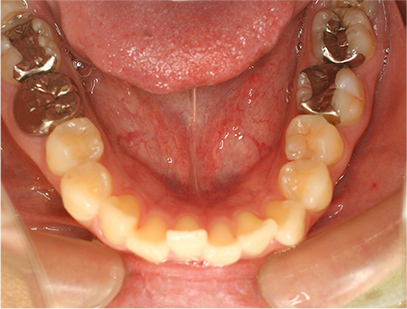

• 下側

• 左側